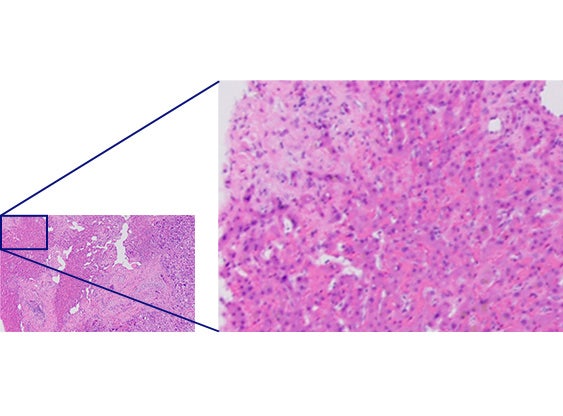

Comparación de resoluciones

Objetivos convencionalesX Line

calidad uniforme desde el centro hasta los bordes

La planitud mejorada permite generar imágenes con calidad uniforme desde el centro hasta los bordes. La alta apertura numérica hace que los objetivos recojan más luz para ofrecer imágenes más brillantes y con mayor resolución. Si complementa los objetivos de la X Line con un microscopio vertical BX53 podrá mejorar en gran medida la calidad de las imágenes.

La aplicación «mosaico» le permite generar imágenes de secciones tisulares completas; sin embargo, si la planitud de la imagen es insuficiente, la imagen en mosaico puede parecer borrosa y presentar una combinación dispar. Los objetivos de la X Line proporcionan imágenes planas uniformes desde el centro hasta el borde, lo que le permite adquirir imágenes en mosaico uniformes y de alta definición. También puede crear una gran imagen en mosaico usando menos imágenes que antes para mejorar su eficacia y ahorrar tiempo.